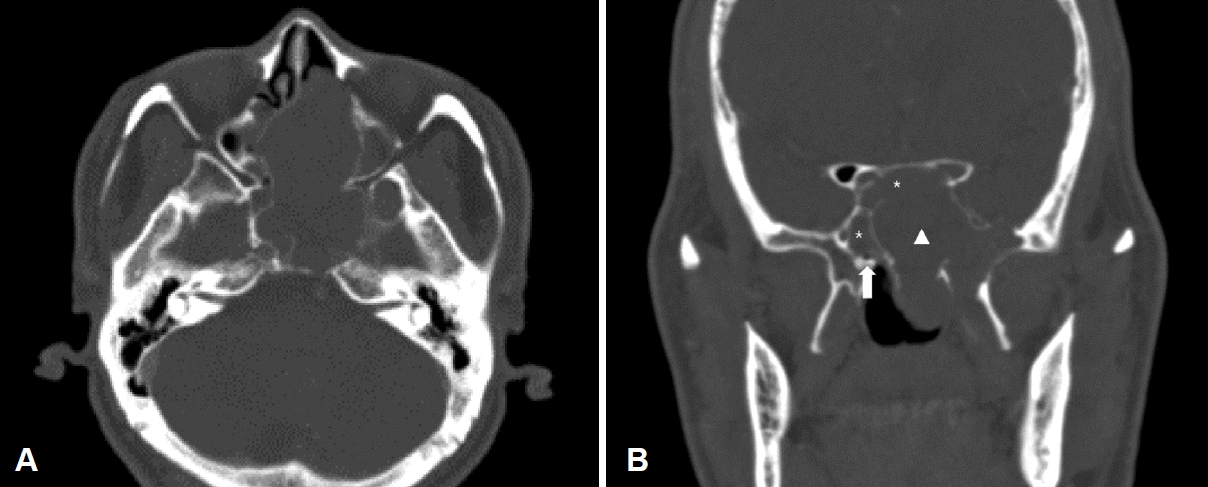

51세 남자 환자가 좌측 비강에서 발견된 종물을 주소로 본원 이비인후과에 내원하였다. 환자는 6개월 전 시작된 좌측 비출혈로 타병원을 처음 방문하였으며 우연히 좌측 비강에서 종물이 발견되어 본원으로 의뢰되었다. 환자는 지적장애 2급으로 일상적인 대화는 가능했으나 정확한 병력 청취에는 어려움이 있었다. 보호자에 의하면 환자는 비폐색과 비루를 호소하였으며 얼굴의 감각 이상이나 안구 건조증은 없었다. 신체 검사에서 피부에 밀크커피색 반점(cafe-au-lait spot)이나 국소 림프절 비대는 관찰되지 않았으며 과거력과 가족력상 특이사항은 없었다. 비내시경 검사상 광택이 나는 백색의 폴립양 종물이 좌측 비강을 가득 채우고 있었다(Fig. 1). 부비동 전산화단층촬영에서 좌측 비강에 약 7.4×5.2×5.3 cm 크기의 경계가 명확하고 조영증강이 잘되지 않은 종물이 관찰되었다. 종물 주변의 뼈는 얇아져 있었으나 골 침범의 소견은 없었으며 좌측 접형동, 사골동, 상악동에 부비동염이 의심되는 저밀도 음영이 관찰되었다(Fig. 2). 부비동 자기공명영상에서 종물은 T1 강조 영상에서 저신호 강도로 나타났으며 T1 조영증강 영상에서는 부분적으로 조영증강된 종물이 관찰되었다. 또한, T2 강조 영상에서는 종물이 고신호 강도로 나타났고 고리 모양의 구조가 고신호 강도로 나타나는 신경 다발 징후(fascicular sign)도 관찰되었다(Fig. 3). 종물에서 조직 생검을 시행하였으며 출혈은 심하지 않았다. 병리검사 결과 신경섬유종이 의심된다는 소견이 보고되었다.

Preoperative contrast-enhanced CT revealed well-defined hypodense mass in the left nasal cavity. The lesion of the nasal cavity showed an expansive growth without bone invasion. Axial view (A), coronal view (B). Both sphenoid sinuses (asterisks), right vidian canal (arrow), and nasal cavity mass (arrowhead).